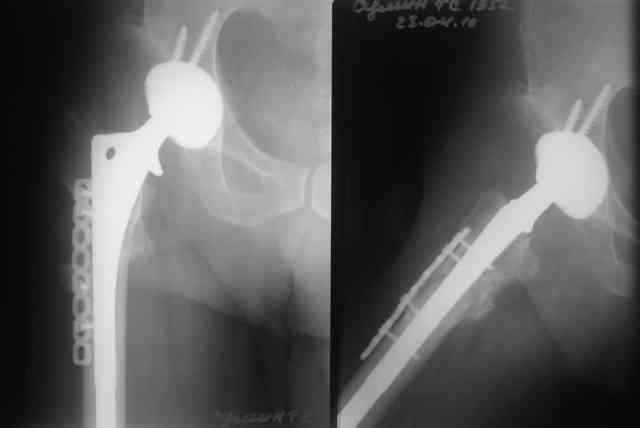

Выполнена одномоментная коррекция деформации, эндопротезирование DePyu Pinnacle-AML. Пластинка с деротационной целью. При использовании ножки с прямоугольным сечением, думаю, можно и без нее.